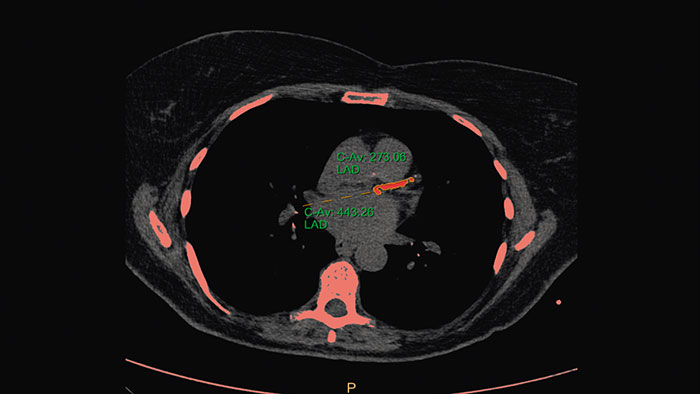

- Calcium Scoring

-

CT Calcium Scoring

One-click 3D calcium segmentation

One-click 3D segmentation and quantification for coronary arteries calcifications including mass, Agatston, and volume scores.

Benefits

- Calcium scoring is achieved by performing automatic calculations on CT HU values in user-defined regions of interest.

- Supports ECG-gated and non ECG-gated images in DICOM format from Philips and other vendors (mass score can only be calculated for Philips CT scanners).

- The application incorporates parameters from the MESA (Multi Ethnic Study of Atherosclerosis) database.